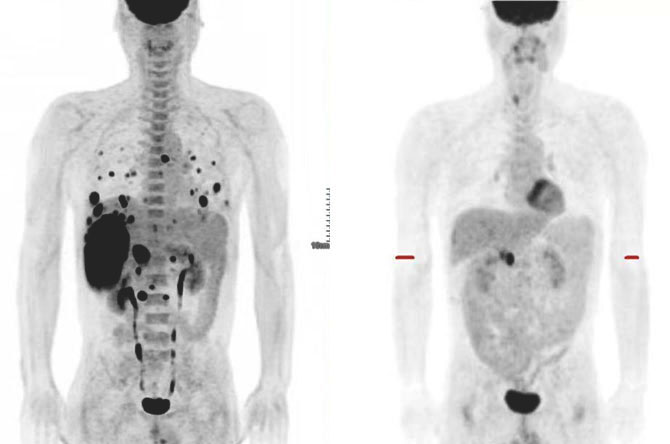

广东省人民医院肝胆外科联合微创介入科、肝移植科、肿瘤内科、放疗科、影像科、检验科、病理科、核医学科和中医科等专科,组建肝脏肿瘤预防、诊断、治疗的多学科诊治平台,紧跟国际和国内最新治疗药物和方案研究前沿,建立以靶向免疫等全身治疗联合介入等局部治疗的序贯全程综合治疗体系,提高晚期患者生存质量和长期生存期,取得良好的效果。我们肝癌治疗的核心理念是个体化、综合化、序贯化和微创化。最终目的是:提高患者生存质量和延长生存期。目前我们有许多晚期全身多发转移的肝癌患者长期高质量生存的病例,积累了丰富的临床实战经验。依此发表多篇有影响力的肝癌基础和临床的文章,参与肝癌相关全国指南的制定,现在是中国医师协会肝癌专业委员会全国委员单位。